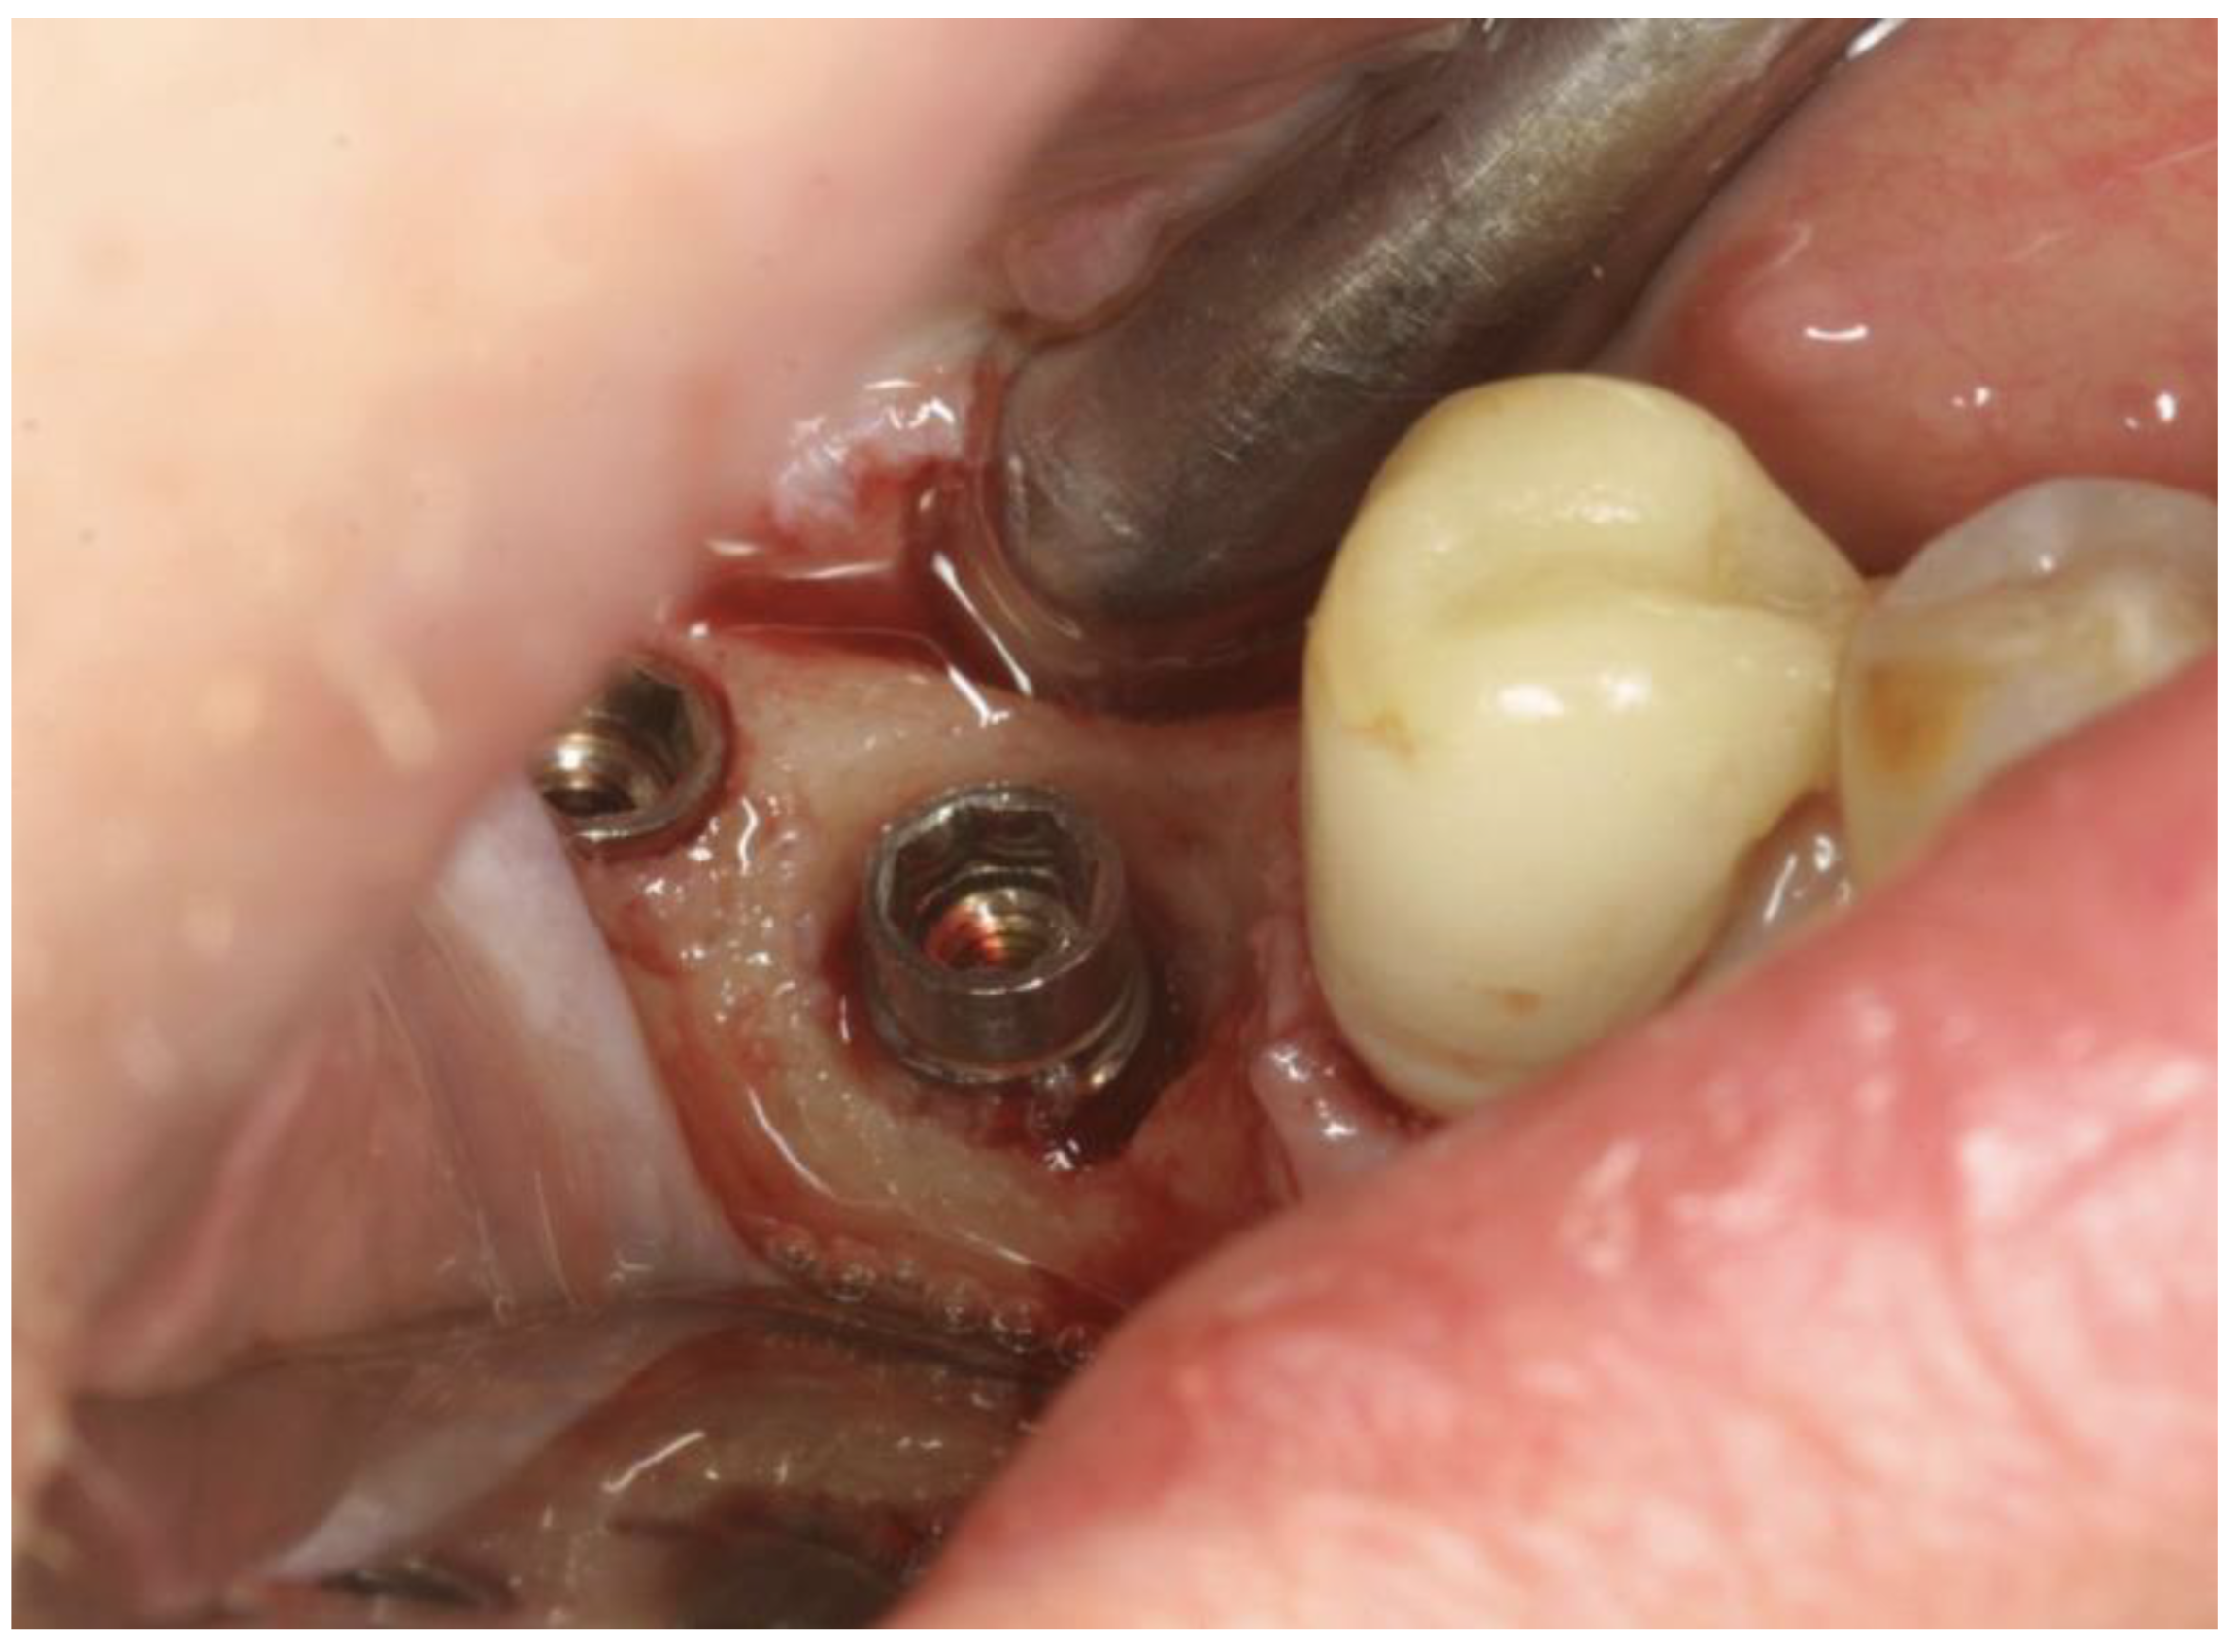

The OHLLT surgical procedure consists of (Figure 2 and Figure 3): local anesthesia; intrasulcular incision for a full thickness periodontal flap; mechanical instrumentation and removal of necrotic tissues with Gracey curettes; ultrasonic instrumentation for supra- and subgingival scaling combined with water–Betadine irrigation (5:1 ratio); air flow device with sodium bicarbonate powder (highly abrasive powder).

Figure 2.

Full Thickness Flap.